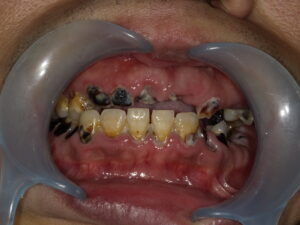

いま現在治療中の症例

治療前

現在の途中経過

仮の歯ですが、歯が入り、噛めるようになっています。

奥歯のかみ合わせを作っている治療の工程になります。